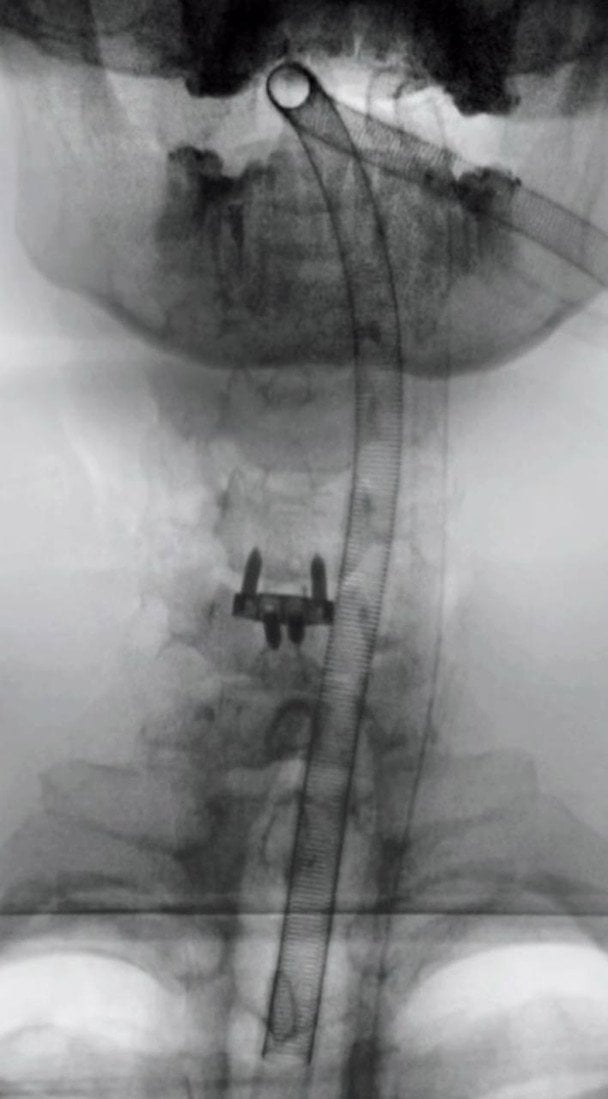

Як з’ясувалося, проблеми почалися ще три роки тому після невдалого сальто. Через травму у нього утворилася грижа в шиї, яка спричиняла постійний біль і навіть періодичне оніміння руки. Медики в Україні та за кордоном довгий час відмовляли його від операції через високий ризик ураження спинного мозку.

«Три роки тому я невдало стрибнув сальто і у мене вилізла грижа в шиї. Відтоді постійний сильний біль і періодичний параліч руки. Я звернувся в лікарню. Мені призначили терапію. Я запитав про операцію, бо хотів жити без цього. У відповідь почув: „Категорично ні. Ризик паралічу — 50 на 50“. Оскільки поруч спинний мозок і ризик зачепити його. Те саме мені сказали лікарі у Польщі, коли я надіслав їм своє МРТ. Мене дуже сильно залякали. Сказали, що оперують тільки в критичних випадках», — зізнався блогер.

Хірургічне втручання минуло успішно — блогеру встановили спеціальний імплант у шию. Після наркозу Ніколас Карма уже вийшов на зв’язок із підписниками та показав перші кадри з операційної та одразу після під час відновлення. На шиї у нього помітний медичний пластир, однак сам блогер почувається значно краще.